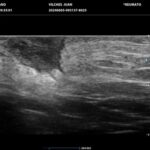

La HS es una enfermedad crónica, inflamatoria inmunomediada, sistémica, recurrente y debilitante de los folículos pilosos terminales con origen en las glándulas apocrinas de estos. Presenta habitualmente lesiones dolorosas, profundas e inflamadas, localizadas más frecuentemente en las regiones axilares, inguinales y anogenitales. El 80% de las lesiones tienen ubicación profunda de difícil acceso al examen físico. Su diagnóstico es clínico pero el ultrasonido (US) de alta resolución con Doppler es un método que cumple actualmente un rol esencial para establecer el diagnóstico, estadificar la enfermedad y detectar actividad, incluso en el caso de lesiones no pesquisadas en el examen físico. También nos permite monitorear el estado y la progresión de la HS, facilitando la evaluación rápida de distintos enfoques terapéuticos. Incluso, los cambios ecográficos pueden modificar la conducta terapéutica.

Hallazgos imagenológicos

Los hallazgos ecográficos más relevantes son el ensanchamiento de folículos pilosos, engrosamiento y ecogenicidad anormal de la dermis, nódulos pseudoquísticos dérmicos, colecciones líquidas y tractos fistulosos. Por otro lado, el US nos permite valorar la localización exacta y extensión de las lesiones, su ecogenicidad, el grado de vascularización al examen Doppler y las eventuales complicaciones, e incluso la modificación de las lesiones en respuesta a la terapéutica instaurada. La HS se estadifica clínicamente mediante la clasificación de Hurley y los hallazgos ecográficos muestran correlación con cada estadio clínico.

El diagnóstico ecográfico resulta de importancia diagnóstica, tal es así que la ecografía de alta resolución y el estudio Doppler han ocupado un lugar preponderante en los últimos años. La ecografía de la piel permite identificar lesiones no encontradas en el examen físico, evaluando de manera fehaciente su extensión anatómica. El empleo de la ecografía en la HS es ideal, ya que el 80% de las lesiones ocurren en las capas más profundas y no en la superficie de la piel. Permite evaluar la localización exacta y extensión de las lesiones, su ecogenicidad, el grado de vascularización al examen Doppler, las eventuales complicaciones, e incluso la respuesta terapéutica.

El estudio ecográfico de alta resolución con Doppler tiene un rol fundamental en la categorización de las lesiones de HS en profundidad, incluso las subclínicas. Debemos incluir al US como técnica de elección para estadificar y monitorear pacientes con HS, ya que nos permite acceder a un diagnóstico rápido de lesiones típicas con las que podremos, en conjunto con la clínica, estadificar y seguir en el tiempo a los pacientes.